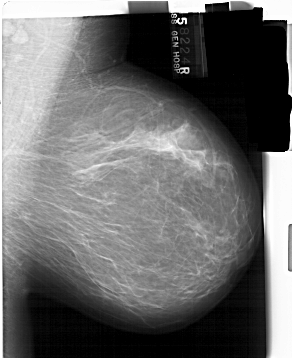

A_1389_1.RIGHT_MLO

RIGHT_MLO LINES 6436 PIXELS_PER_LINE 5251 BITS_PER_PIXEL 12 RESOLUTION 43.5 NON_OVERLAY